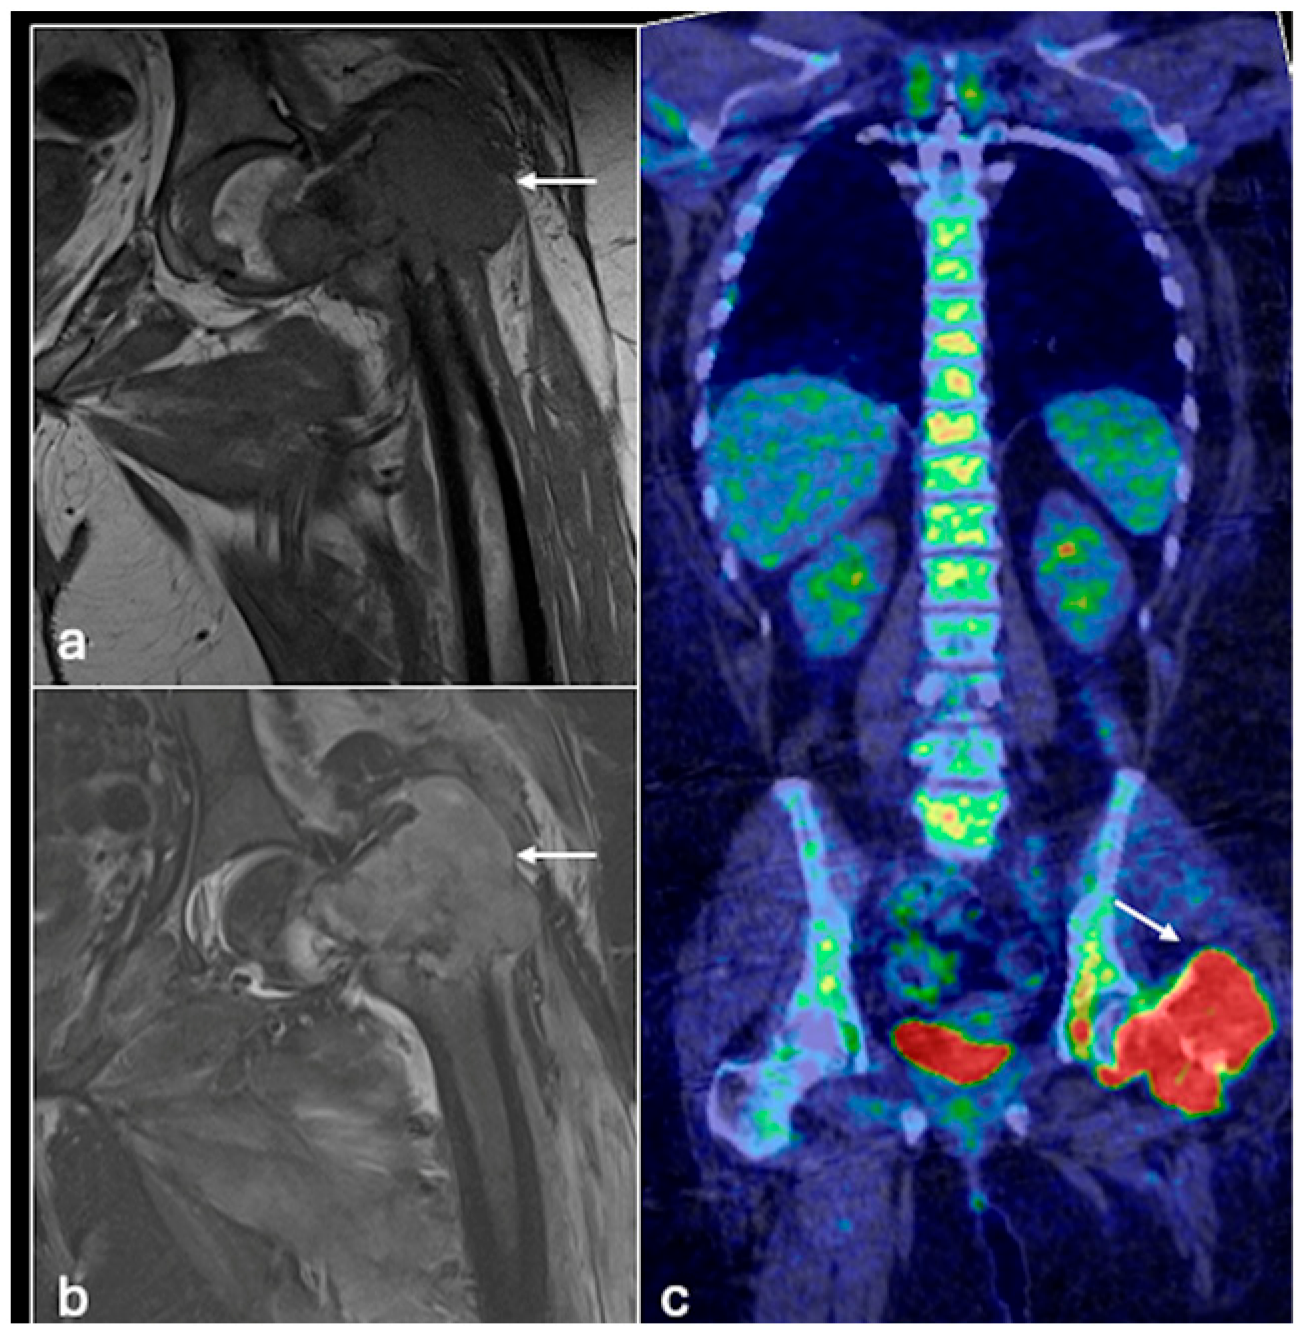

4.1. Osteosarcoma